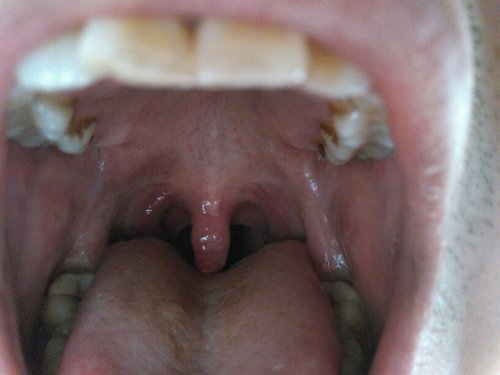

嗓子感覺(jué)糊了一層粘液,原因、緩解與預(yù)防策略,嗓子糊粘液,成因、緩解及預(yù)防策略

摘要:嗓子感覺(jué)糊了一層粘液可能是由于多種原因引起的,如感冒、過(guò)敏或慢性喉炎等。為了緩解這種癥狀,可以嘗試多喝水、避免過(guò)度用嗓和保持室內(nèi)空氣濕度。預(yù)防策略包括保持良好的生活習(xí)慣,增強(qiáng)免疫力,避免接觸過(guò)敏源等。如有持續(xù)不...